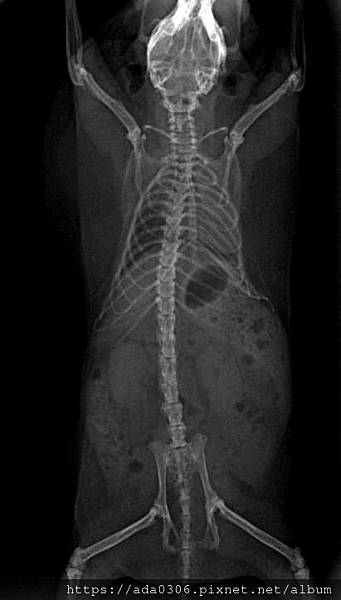

圓呼呼的團團,非常不配合照X光,所以讓她吸一口麻醉睡了幾秒,一拍完就自動醒過來了,時間抓得剛剛好。

在其他項目的檢查中,團團各部位都正常,除了有駝背。X光下顯示出許多老化跡象,還好有提早發現,表示老年健檢是很重要的!

心臟有變大,應該是左心房,反映出心臟功能變弱,目前不用投藥,但建議補充心臟保健品。

脊椎的椎間盤有三四節已經退化黏在一起了,那部份就不能彎曲,走路會僵直,這也是駝背的原因。

腎臟與肺臟的尺寸正常無腫大,團團雙腿膝蓋也是退化性關節,肚子內有食物和一些空氣,應該是吃東西時一併吞下的。